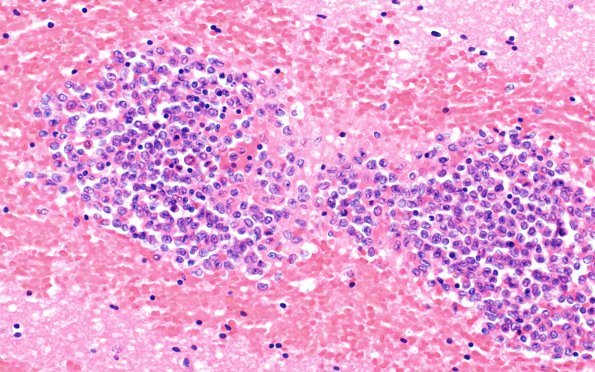

Washington University Experience | NEOPLASMS (HEMATOLYMPHOID) | Granulocytic Sarcoma | 3B4 Leukemic Nodules (Case 3) 40X 1

Higher magnification images of the nodule of image #3B1 demonstrating its myeloblastic center. Surrounding neural tissue showed acute white matter edema with ameboid glia and some karyorrhexis adjacent to the nodules (H&E)